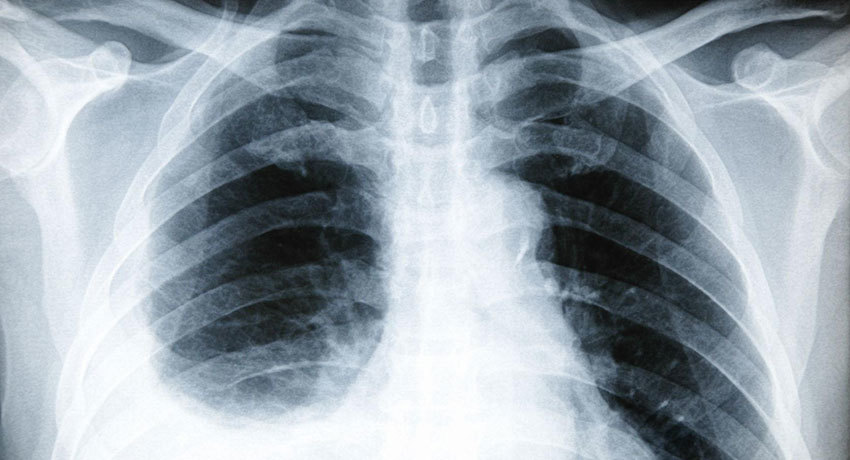

С помощью рентгена можно хорошо увидеть скопление жидкости, оценить ее объем, обнаружить опухоль, поражение лимфоузлов.